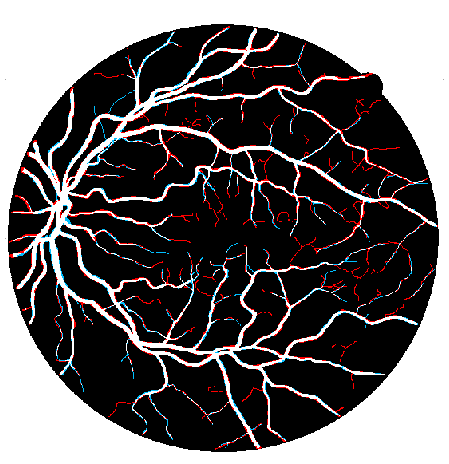

4.1 Validation of the Base System

We started by evaluating our Base System regarding data augmentation, prediction and regularization. The results of each variant are shown in Table 3, while the probabilistic predictions can be seen in Fig. 4. All tests were performed under the same conditions, with the only source of variability being the component under study.

Considering the Base System as the reference, we can see that reducing the number of patches by four strongly deteriorated the results in terms of Acc and AUC. Besides this, either when using original or elastic patches to keep the initial number of samples, the differences to the reference remained almost the same. Looking directly at Fig. 4, we notice that these approaches favored the simultaneous appearance of FN and FP, with elastic patches leading to greater tortuosity in the detected vessel segments. Overall, this hints that the network benefited the most from the information encoded by the rotations. Another important note is related to the way those rotations were presented to the network. Recalling section 2.4, we have seen that some data augmentation strategies designed for FC-CNNs (Dieleman et al.,, 2016; Worrall et al.,, 2016) require the rotated versions to be arranged consecutively. The Consecutive Rotations test hints that a deterministic proximity between the rotated patches is detrimental to the performance of the FCN, with the network showing more difficulties in detecting vessel segments as can be seen in Fig. 4.

Here, we compare the Base System, which uses our multiple prediction scheme, with the Simple Prediction variant. As can be seen in Table 3, the Base System performed better both in terms of Acc and AUC. Moreover, comparing the predictions of both approaches (Fig. 4), we notice that the multiple segmentation scheme makes the model less prone to FP, which is particularly important in medical applications. As a point of note, even if the changes in the mean values were slighter, statistically significant differences were found between the two methods.

Still having the Base System as a reference, we can see that the standard strategy led to a statistically significant drop in terms of Acc and AUC (Table 3). Overall, the predictions are quite similar, but the model seems to detect fewer vessel segments when the standard dropout is applied (Fig. 4).